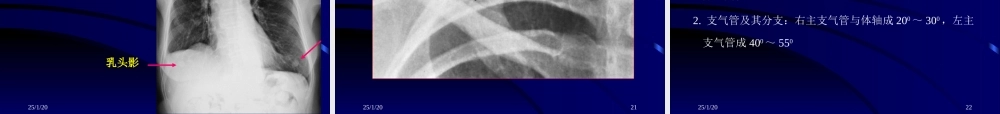

25/1/201呼吸系统影像诊断河南大学淮河临床学院医学影像教研室李长波25/1/202呼吸系统一、检查方法二、正常胸部影像表现三、基本病变表现四、常见病的影像诊断25/1/203一、检查方法(一)常规X线检查透视胸片体层摄影(肺门、病灶)高千伏摄影支气管造影(二)CT检查(平扫、增强)(三)MR检查(平扫、增强)25/1/204透视透视方法简单多体位、动态观察不易发现细小病变没有永久记录25/1/205RADIOGRAPHYRADIOGRAPHY摄影摄影正位(P-A位A-P位)侧位(左右侧)前弓位卧位点片25/1/206Frontalview暗盒CASSETTE正位胸片优点:射线较透视少;有永久记录,便于复查。25/1/207Lateralview暗盒CASSETTEX-ray侧位胸片缺点:不能动态观察25/1/208高千伏摄影≥120kv、5-7mAs减少胸壁、软组织及肋骨对肺部病变的干扰。25/1/209支气管造影25/1/201025/1/201125/1/2012二、正常胸片表现及变异25/1/2013Title:幻灯片1•Size:8291•LastModified:Thu,15Jun200603:23:18GMT一、正常X线表现(1)㈠胸廓(正位)1.骨骼⑴肋骨:肋软骨钙化呈条带状或斑点状常见变异:颈肋、叉状肋、肋骨联合⑵锁骨:内端下缘半圆形凹陷为菱形窝⑶肩胛骨:肩胛骨下角可出现二次骨化中心,勿误为骨折⑷胸骨:大部与纵隔影重叠⑸胸椎:1~4胸椎清楚可见,其余隐约可见25/1/201425/1/2015Title:幻灯片1•Size:4177•LastModified:Thu,15Jun200603:23:08GMT胸廓骨骼(线图)胸廓骨骼(线图)胸廓骨骼(线图)胸廓骨骼(线图)25/1/2016Title:Title:幻灯片幻灯片1•1•Size:Size:4403•4403•LastModified:LastModified:Thu,15Jun200603:23:10GMTThu,15Jun200603:23:10GMT颈肋(图)颈肋(图)25/1/2017肋骨联合25/1/2018Title:Title:幻灯片幻灯片1•1•Size:Size:6942•6942•LastModified:LastModified:Thu,15Jun200603:22:38GMTThu,15Jun200603:22:38GMT一、正常X线表现(2)㈠胸廓(正位)2.软组织:⑴胸锁乳突肌和锁骨上皮肤皱褶⑵胸大肌⑶女性乳房和乳头⑷伴随阴影25/1/2019Title:幻灯片1•Size:3640•LastModified:Thu,15Jun200603:23:10GMT软组织(线图)软组织(线图)25/1/2020乳腺影乳头影25/1/2021Title:Title:幻灯片幻灯片1•1•Size:Size:3661•3661•LastModified:LastModified:Thu,15Jun200603:23:12GMTThu,15Jun200603:23:12GMT软组织(图)软组织(图)25/1/2022Title:Title:幻灯片幻灯片1•1•Size:Size:8587•8587•LastModified:LastModified:Thu,...